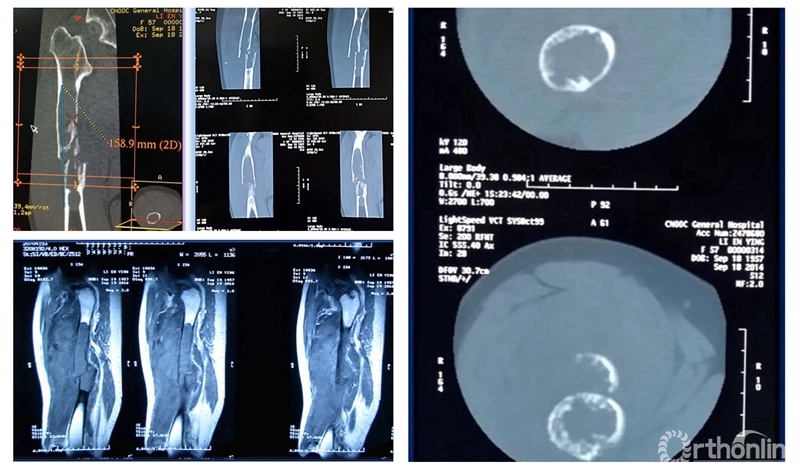

患者女性,68岁,乳腺癌病史,右股骨中段病理性骨折,股骨长段溶骨性破坏,并有跳跃病灶。病变的长度为16cm,病灶近端在小转移水平,因为近端髓腔柄较短,故选择A区骨干假体。经病理诊断为转移性腺癌,术后2周患者拆线后即可离床活动。

术前资料